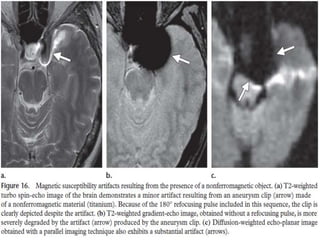

MAGNETIC SUSCEPTIBILITY ARTEFACT

• These artefacts results from local magnetic field

inhomogeneities introduced by a metallic object into the

otherwise homogeneous external magnetic field B0.

• These local magnetic field inhomogeneities are known as

magnetic susceptibility and are a property of the object being

imaged

• More prominent in Gradient echo sequence than Spin echo

sequence .

• Corrected by removing all metals and use of soin echo